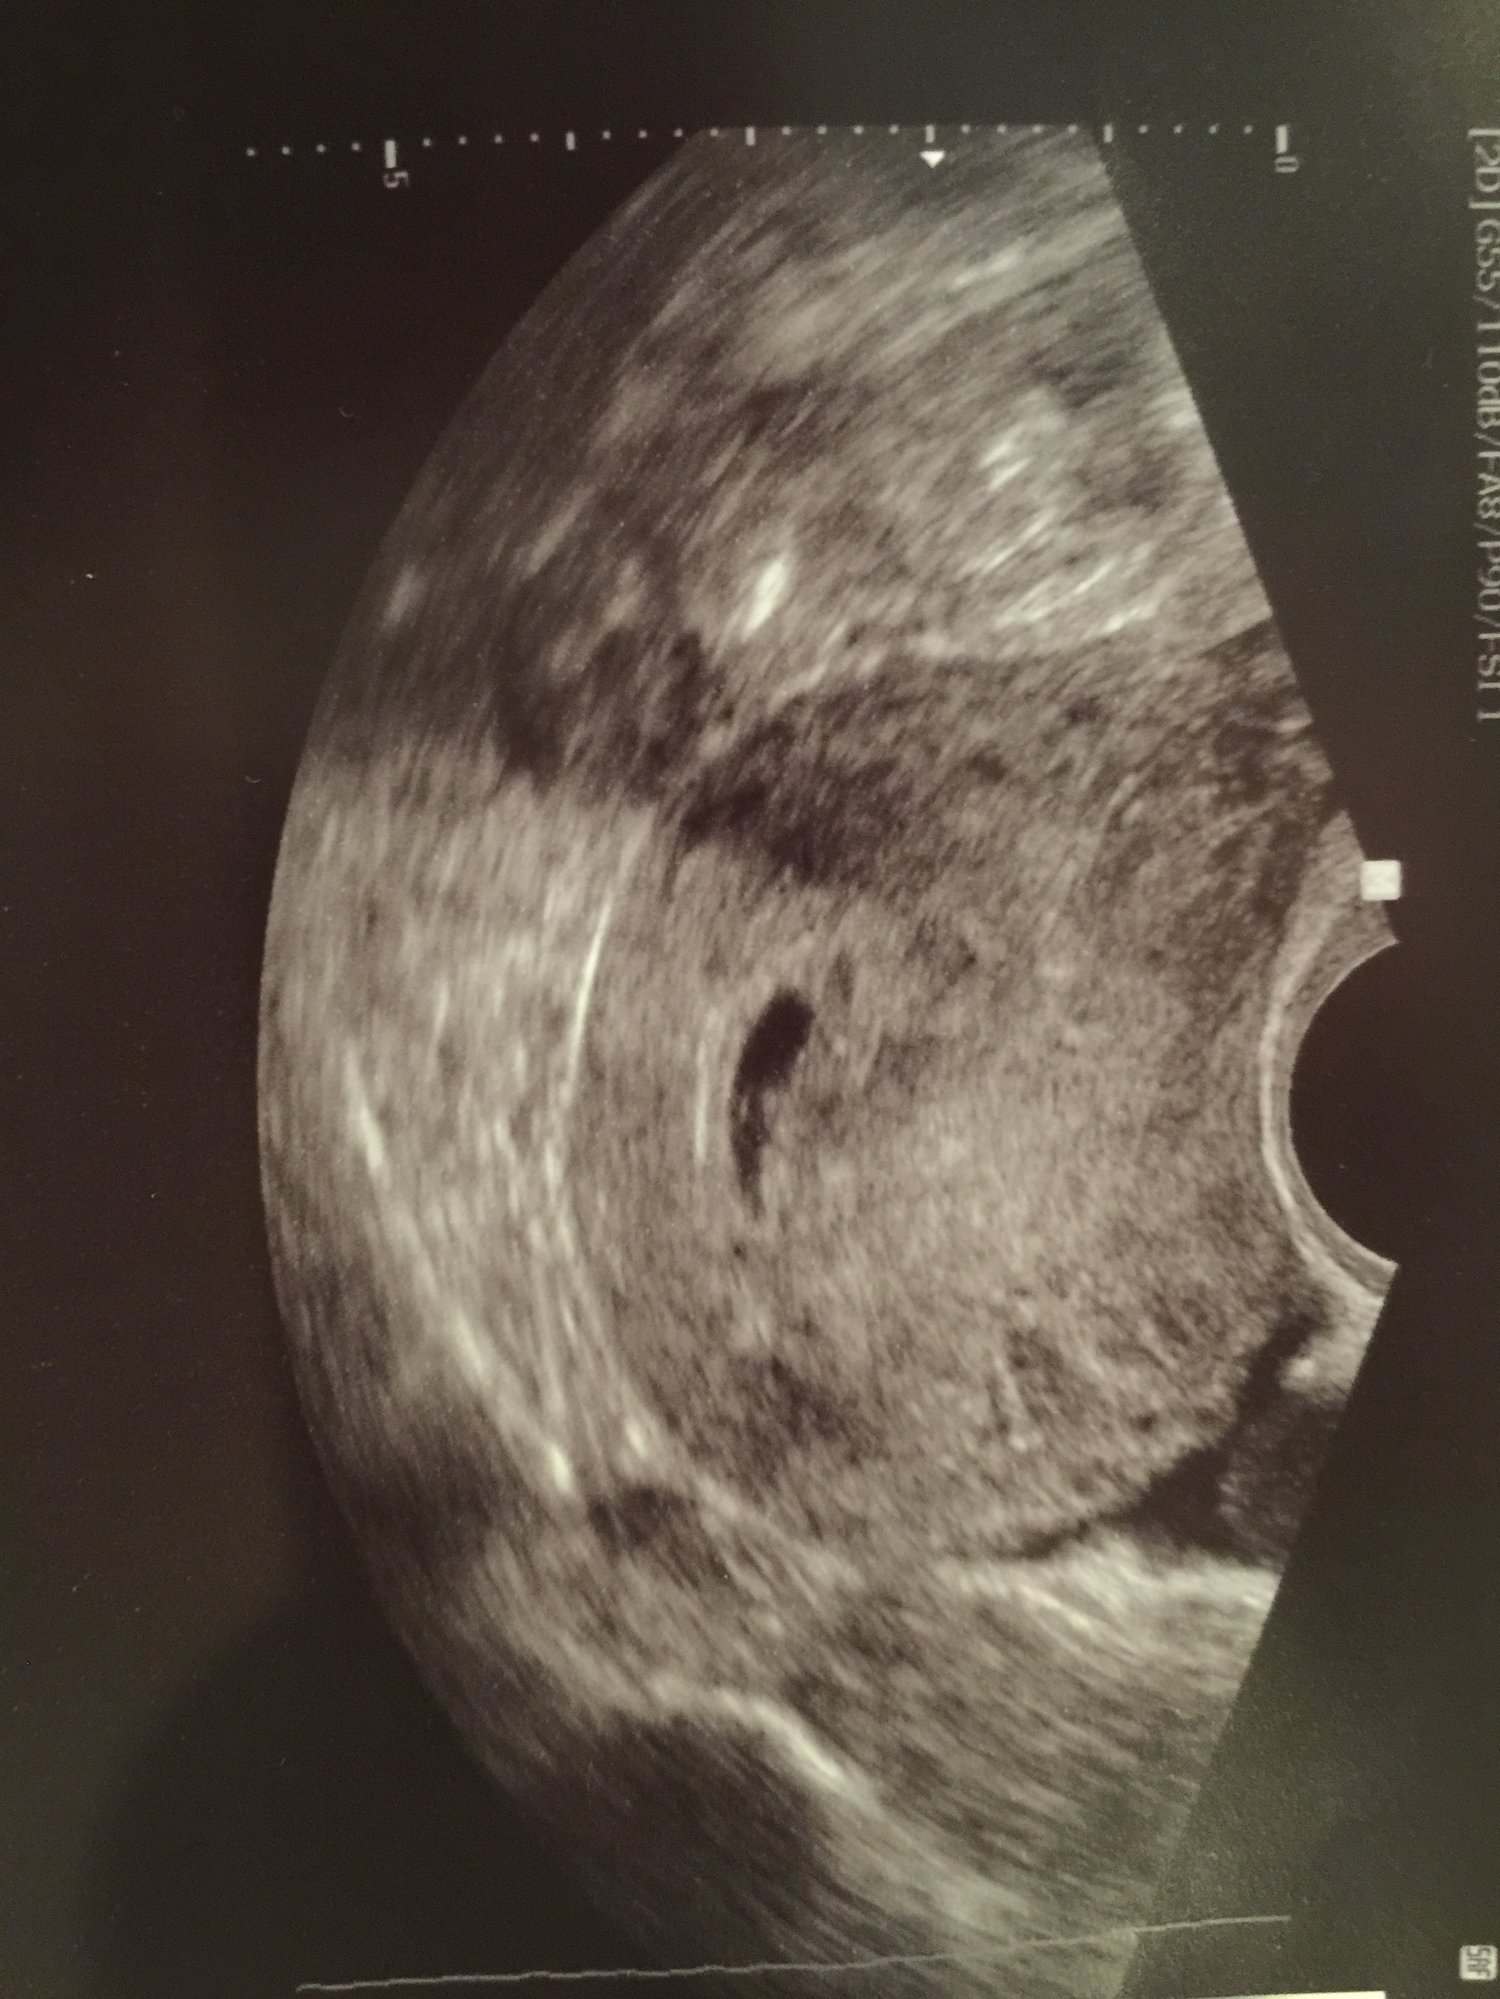

Ok, I have to share. Since my last pregnancy ended in loss, I've been obsessing over this for the past two days.This is from Wed. The larger sac was measuring two days ahead at 5w5d (yolk sac was visible although it's not in this pic) and they didn't measure the smaller sac. Anyone have experience with early twins? RE said it's possible it could've implanted later, it could be a vanishing twin or it could be a fluid pocket. I have another u/s on Monday but that's like an eternity away.

I'm a giant bundle of anxiety and nerves. I can't help but check for blood each time I go to the bathroom and I keep thinking that since there's potentially two in there, if something happens to one, at least I have another. It's so messed up what miscarriage does to your mind. Sigh.

@MamaWino Hi Pickle shaped sac buddy!! Haha. I don't have any experiences with twins. That would be exciting though!! Now I'm dying to know what happens for you on Monday!! I can say that my gestational sac changed A LOT in a week, so it is possible that spot is a sac a few days behind.

Lol, at pickle shaped sac buddy, @MrsBinPA! And yeah, I'm dying for Monday to get here... staying busy to keep my mind off of it is proving pretty difficult! I JUST WANT TO KNOW! I'm ridiculously impatient so this waiting game is killing me.

ETA: I saw your HCG level in the beta thread. Seems pretty darn high to me! Much higher than where I am.

And re: hCG levels, yeah, they've been high from the start which would make sense for twins but I'm trying not to read too much into it since they can vary so much.